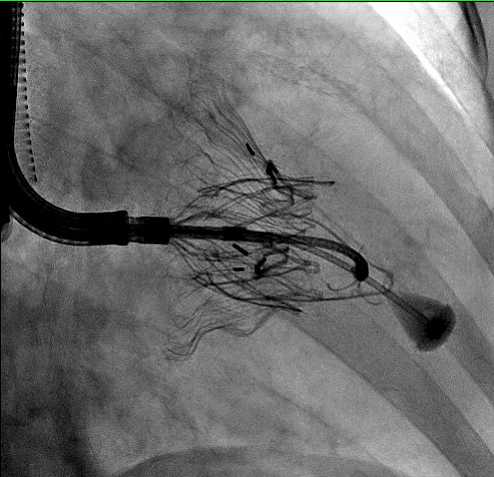

Post-Market Real World Outcomes in WATCHMAN FLX™ Pro Left Atrial Appendage Closure (LAAC) Device

Luigi Di Biase, MD

Assessment of Safety and Effectiveness in Treatment Management of Atrial Fibrillation With the BWI IRE Ablation System (AdmIRE)

Luigi Di Biase